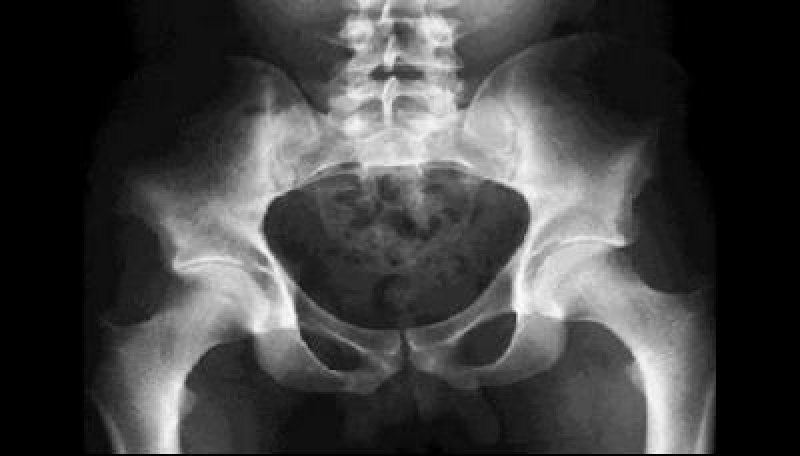

Vorig voorjaar was ik voor een onschuldig klachtje bij de gynaecoloog. De arts-assistent deed inwendig onderzoek en vond, bij toeval, een beginstadium van baarmoederkanker.

Ik schrok natuurlijk ontzettend. Ik moest worden geopereerd, waarbij baarmoeder en eierstokken weggenomen werden. Niet niks. Kanker, je zal de diagnose maar krijgen.

Toen de uitslag van het weefselonderzoek (de zogenaamde ‘PA’-uitslag) binnenkwam en alles verwijderd bleek te zijn en er verder geen chemo of bestraling nodig was, was ik natuurlijk opgelucht. Maar het ging nog verder. Ik zag de hele gebeurtenis eigenlijk direct als een zegen.

Dankzij kanjers van artsen was één operatie voldoende om me er van te verlossen.

De hormoongerelateerde migraine, waar ik al jarenlang last van had, zou ik voortaan kwijt zijn. En doordat de eierstokken ook waren verwijderd, zou de overgang, waar ik sinds kort middenin zat, versneld afgewerkt worden.